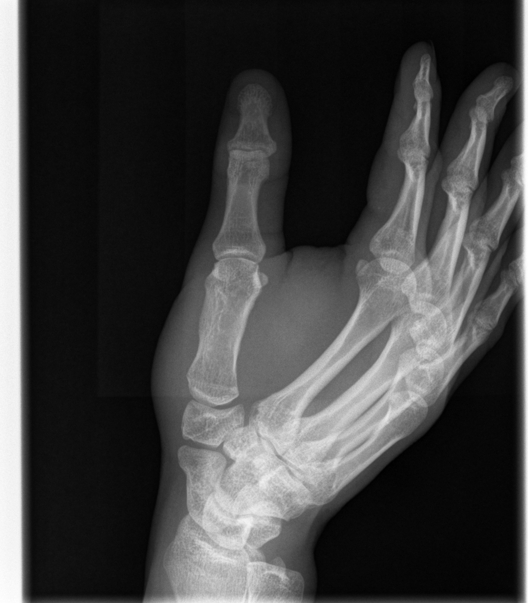

Broken Hand

This was just a hairline fracture that I managed to get from a soccer game. I thought it was pretty cool that I was given all of the digital copies.

Here we see and x-ray of someone's wrist and their hand.